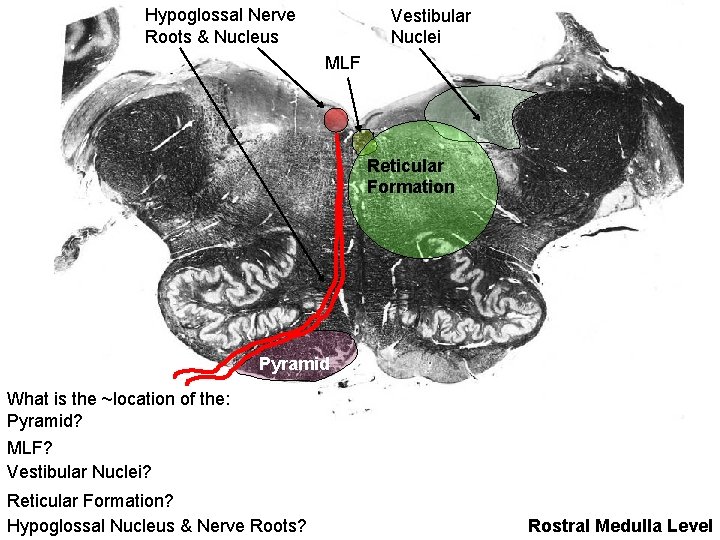

Hypoglossal Nerve Roots & Nucleus Vestibular Nuclei MLF Reticular Formation Pyramid What is the ~location of the: Pyramid? MLF? Vestibular Nuclei? Reticular Formation? Hypoglossal Nucleus & Nerve Roots? Rostral Medulla Level